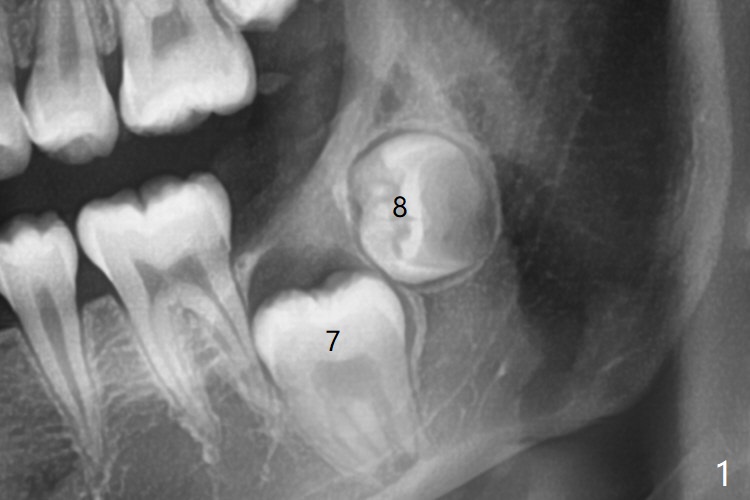

Treatment planning of surgical access to the impacted 7 (Fig.1) before CT analysis (to be canceled due to finance) include extraction of 8 (Fig.2) and removal of the bone coronal to 8 (Fig.3 red) so that there will be no bony block to 7 eruption (Fig.4). Place PRF or collagen plug in 8 socket to facilitate healing (Fig.3). Attach a retraction chain to the occlusal or buccal surface of 7 (Fig.6 pink) whenever it is convenient in term of hemorrhage and access (as mesial as possible). Remove 16 niti wires for brushing when the patient arrives. Cut 18 ss wire longer in the LL end (Fig.6 green to be bent to hook power chain (yellow)). Incision is shown as red in Fig.5. After 3 month delay, the thick buccal plate is removed from LL8 (1st) and 7 (2nd in sequence, as compared to Fig.2) to expose these unerupted teeth. In fact CT is not taken to decrease budget on the divorcing parents. A retraction chain is placed before extraction of LL8 with an intention to reduce hemorrhage (Fig.7). Although extraction requires several sectioning of the tooth, hemorrhage is mild to moderate. Instead of PRF and sticky bone (as compared to Fig.3), Osteogen plug is placed in the socket (Fig.8 OP). The bony septum between the 2 sockets is intentionally kept in place (*). 事实的确这样发生(图九:*)。埋伏牙不仅上移(^),而且远中移动(>),因为牵引方向(红虚线(橡皮筋),挂在上牙弓丝(图九:20ss:图十:18ss(之前))远端勾,积极牵引三个星期)。下次左上7放置舌侧纽扣,让病人更换橡皮筋。其实纽扣粘不住,上牙弓丝远中勾也不现实,只能使用橡皮筋挂在左上6,经常断。术后6个月,左下7继续上移(图十一)。这种低效率牵引仍然有效,牙齿继续上移,牙根长长(图十二:空箭头),但是受到左下6远中阻挡(*),所以下次在左上7咬合面装置舌侧纽扣和closed spring,改善牵拉方向(红箭头)。